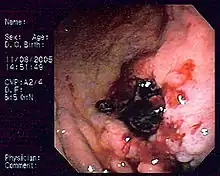

Lymphome gastrique du MALT.